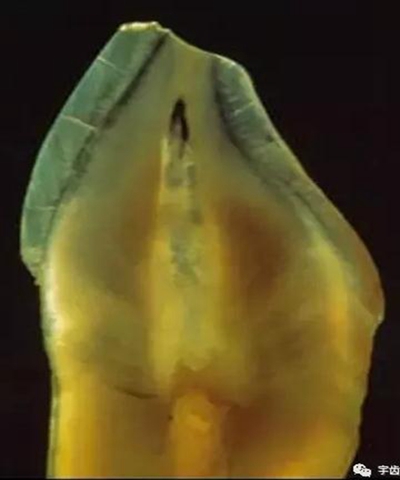

牙體解剖知識

牙體各個面的解剖厚度